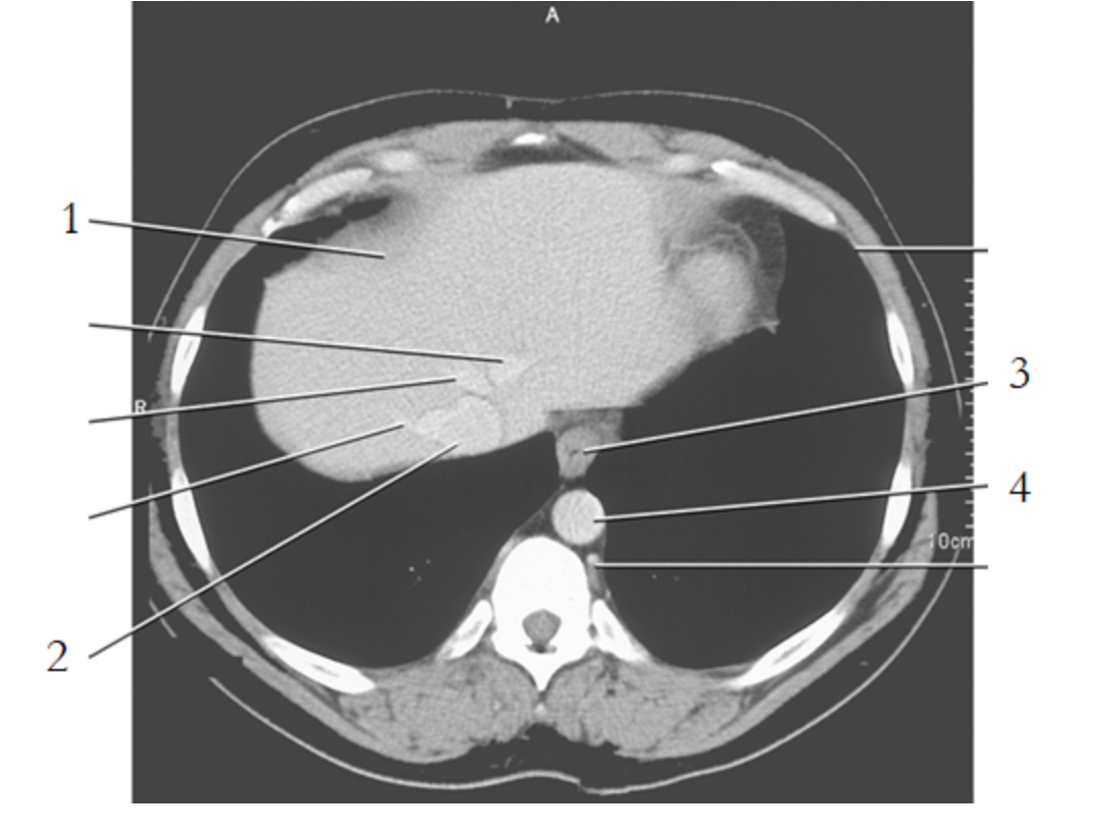

1

liver

11

stomach

12

spleen

9

crus of diaphragm

8

IVC

13

pancreas tail

16

kidney

14

gallbladder